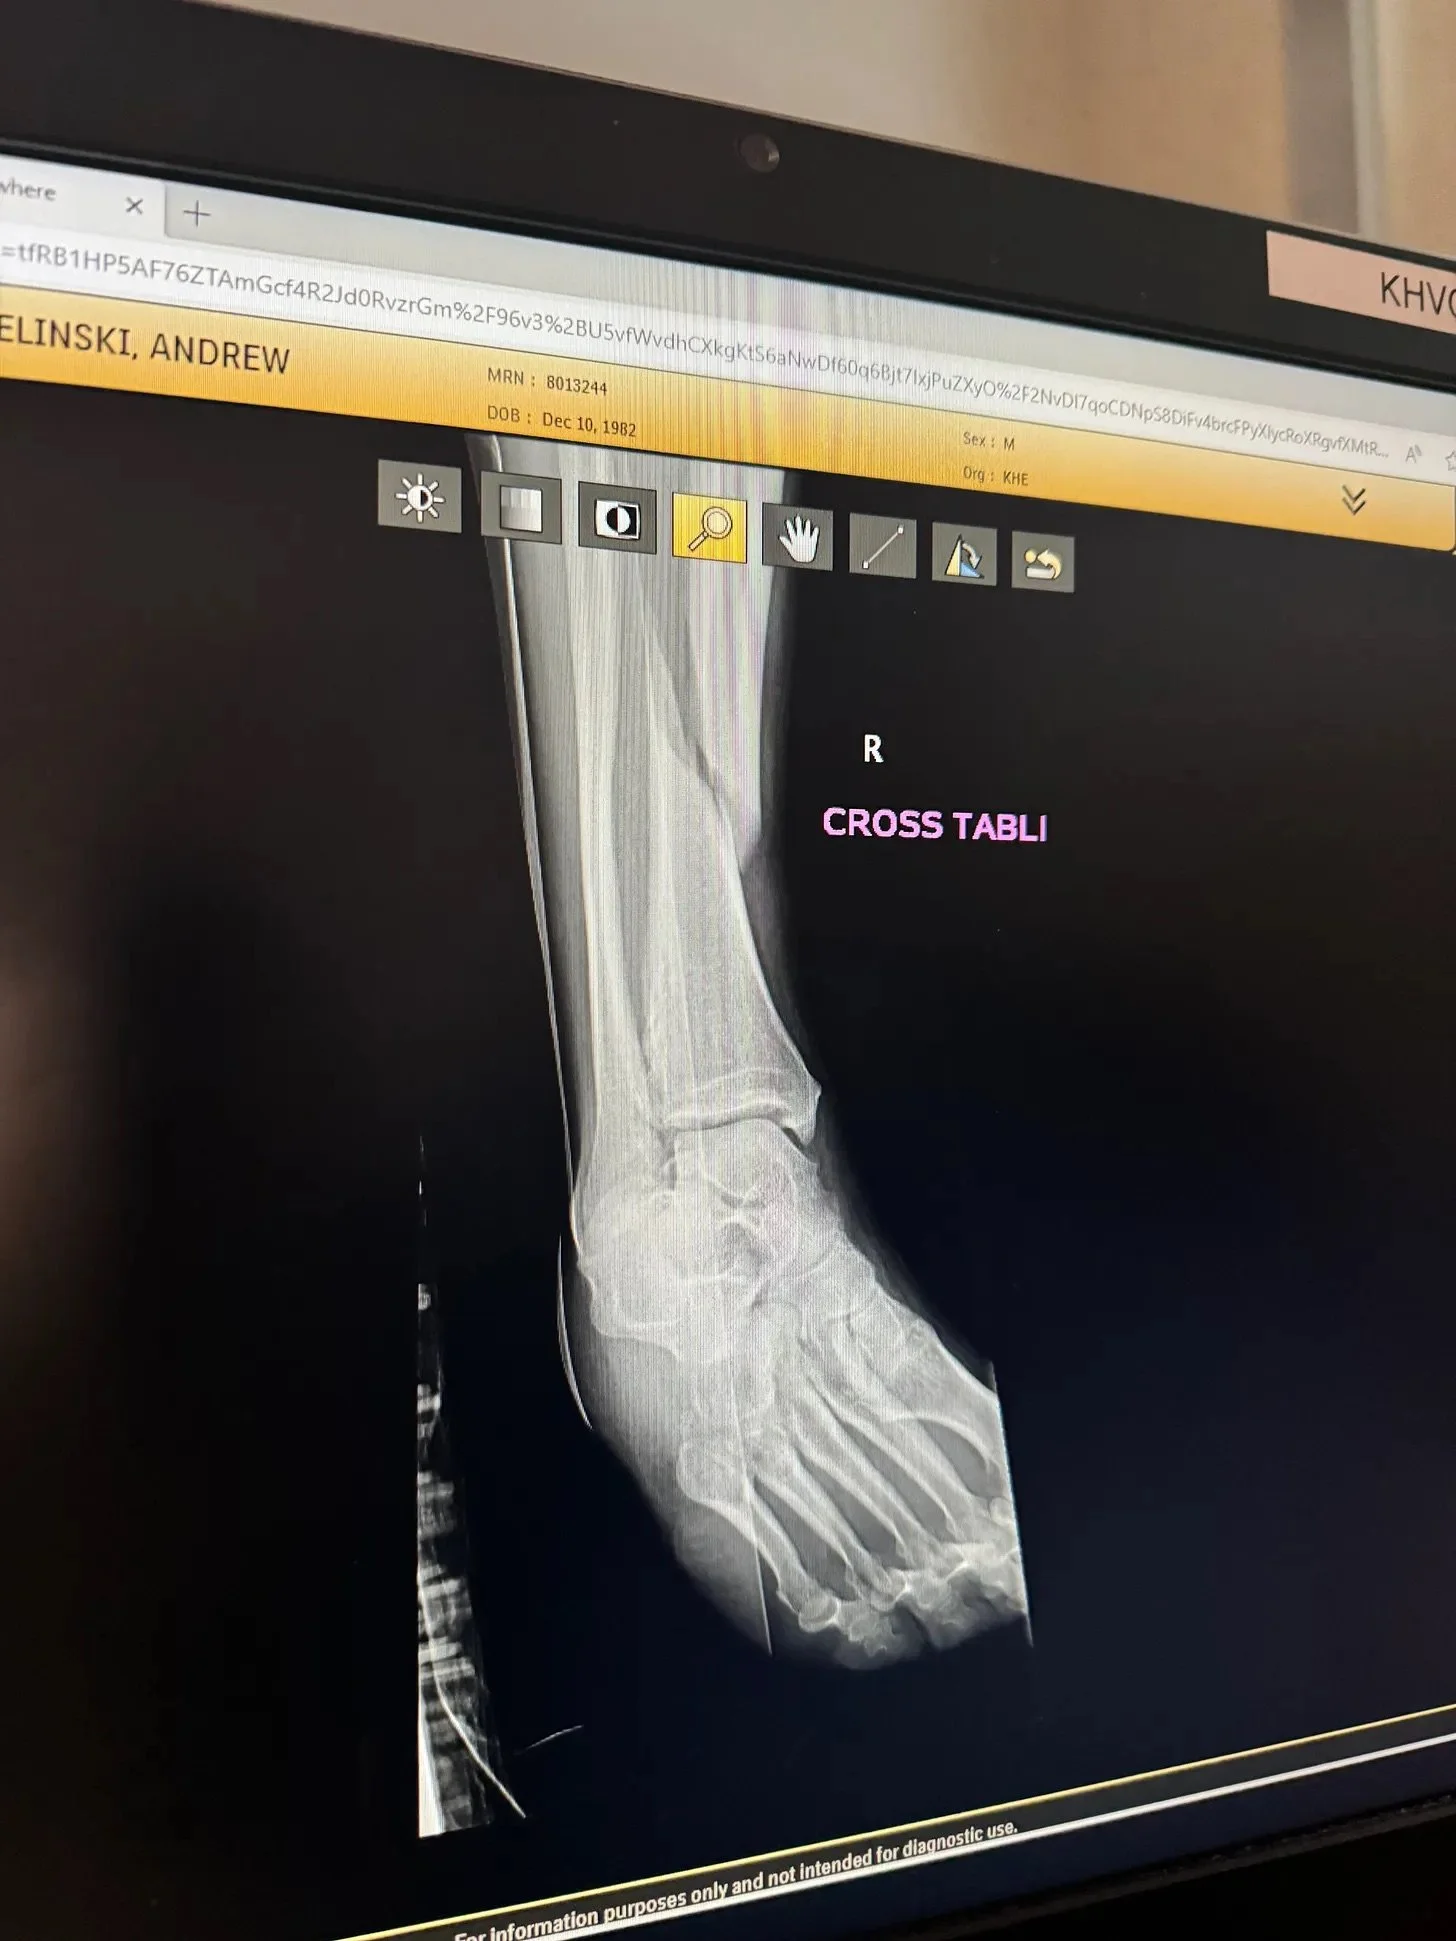

Miles will resume, trust me, I’m an endurance athlete for life. And those miles might vary greatly across disciples. But more importantly, I hope I can inspire thru my journey and share what I’ve learned. Otherwise breaking your tibia and getting a metal “nail” shoved down the length of your bone aint worth.